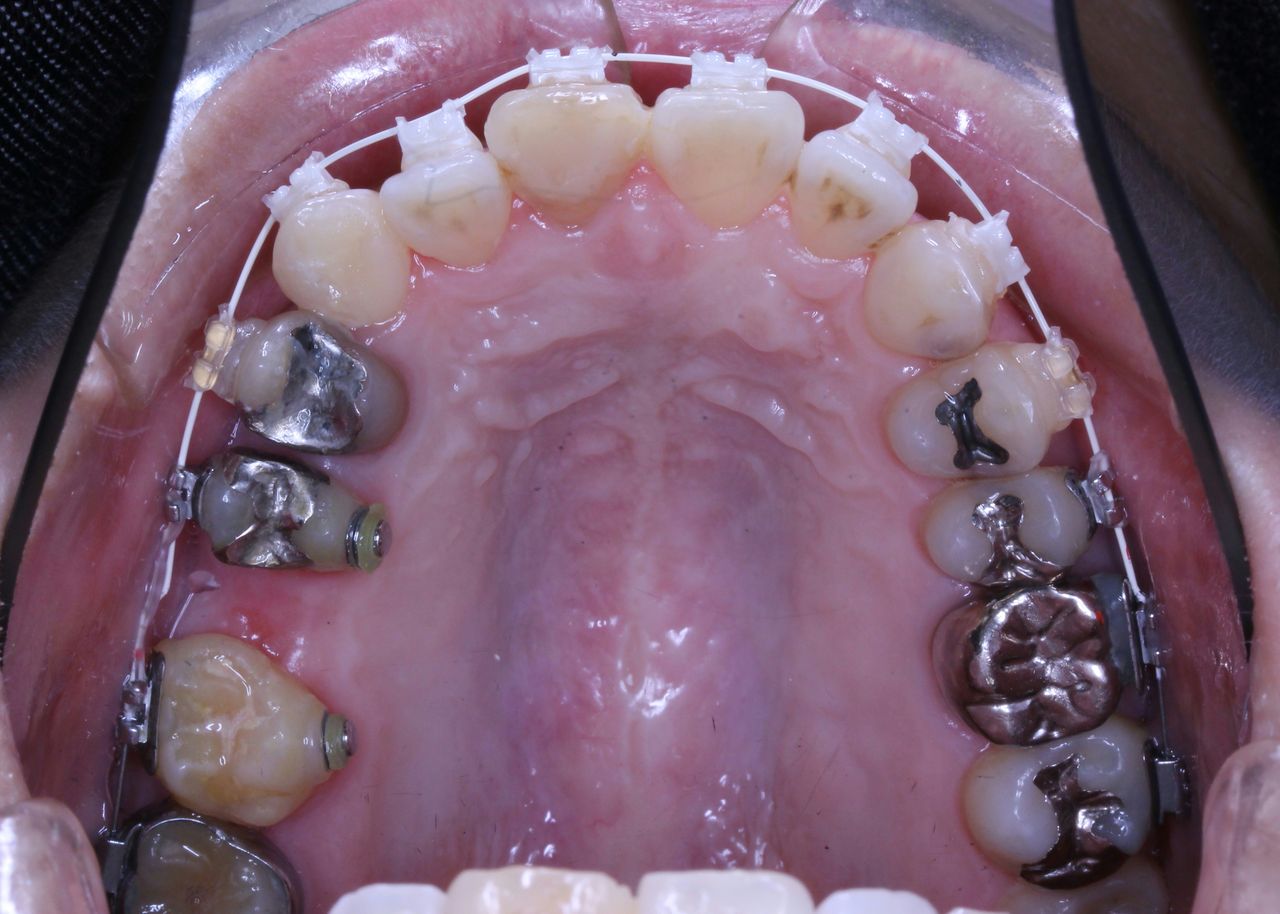

その患者さんの数年前の画像です

現在は他のクリニックで歯列矯正を一切しない方法で治療を開始しており、かみ合わせがおかしくうまくいっていないような気がするとのことでコメントを求めての来院でした。